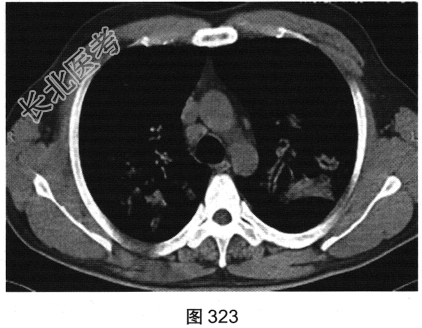

- [材料题] 患者男性,30岁,发作性咳喘3年,吸入冷空气后鼻塞、流黄白色脓涕,外院予环丙沙星治疗后症状缓解,其后鼻塞,夜间睡眠中喘憋反复发作;咯血、发热1周,以傍晚和夜间为著,体温最高为38.5℃,伴畏寒及周身疼痛,痰中带血,为鲜红色,伴胸痛、咳嗽,喘憋明显。胸部CT检查如图319~图324所示。

- 多项选择题3.[提示]患者血常规示嗜酸性粒细胞明显升高,红细胞沉降率、CRP升高, ANCA(-),尿常规示蛋白尿、血尿。既往3~5年前有多次接触强烈刺激性气体(玻璃胶)暴露史、过敏史, 鼻窦炎病史2年。肺功能检查示阻塞性通气功能障碍。根据上述临床资料与CT表现特点,患者最可能的诊断为( )

A、淋巴瘤

B、血管炎

C、慢性嗜酸性粒细胞性肺炎

D、病毒感染

E、真菌感染

F、炎性肺癌